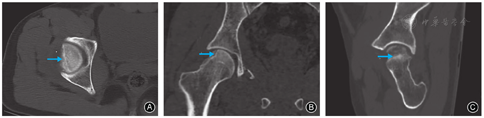

男,28岁,快递员。因骑电动车撞击花坛致伤2 h入院。急诊体格检查:右髋部疼痛、右下肢外展外旋畸形伴活动受限,远端肢体感觉及循环可。急诊摄骨盆正位X线片示右髋关节前脱位,股骨头塌陷(图1A);即行髋关节脱位手法闭合复位以避免股骨头脱位时间过长影响血供,复位后摄X线片证实右侧髋关节已复位(图1B)。骨盆CT示患者右侧股骨头外前象限压缩(图2);三维重建示股骨头塌陷约2.5 cm×3.0 cm,压缩体积略大于股骨头体积的10%(图3)。